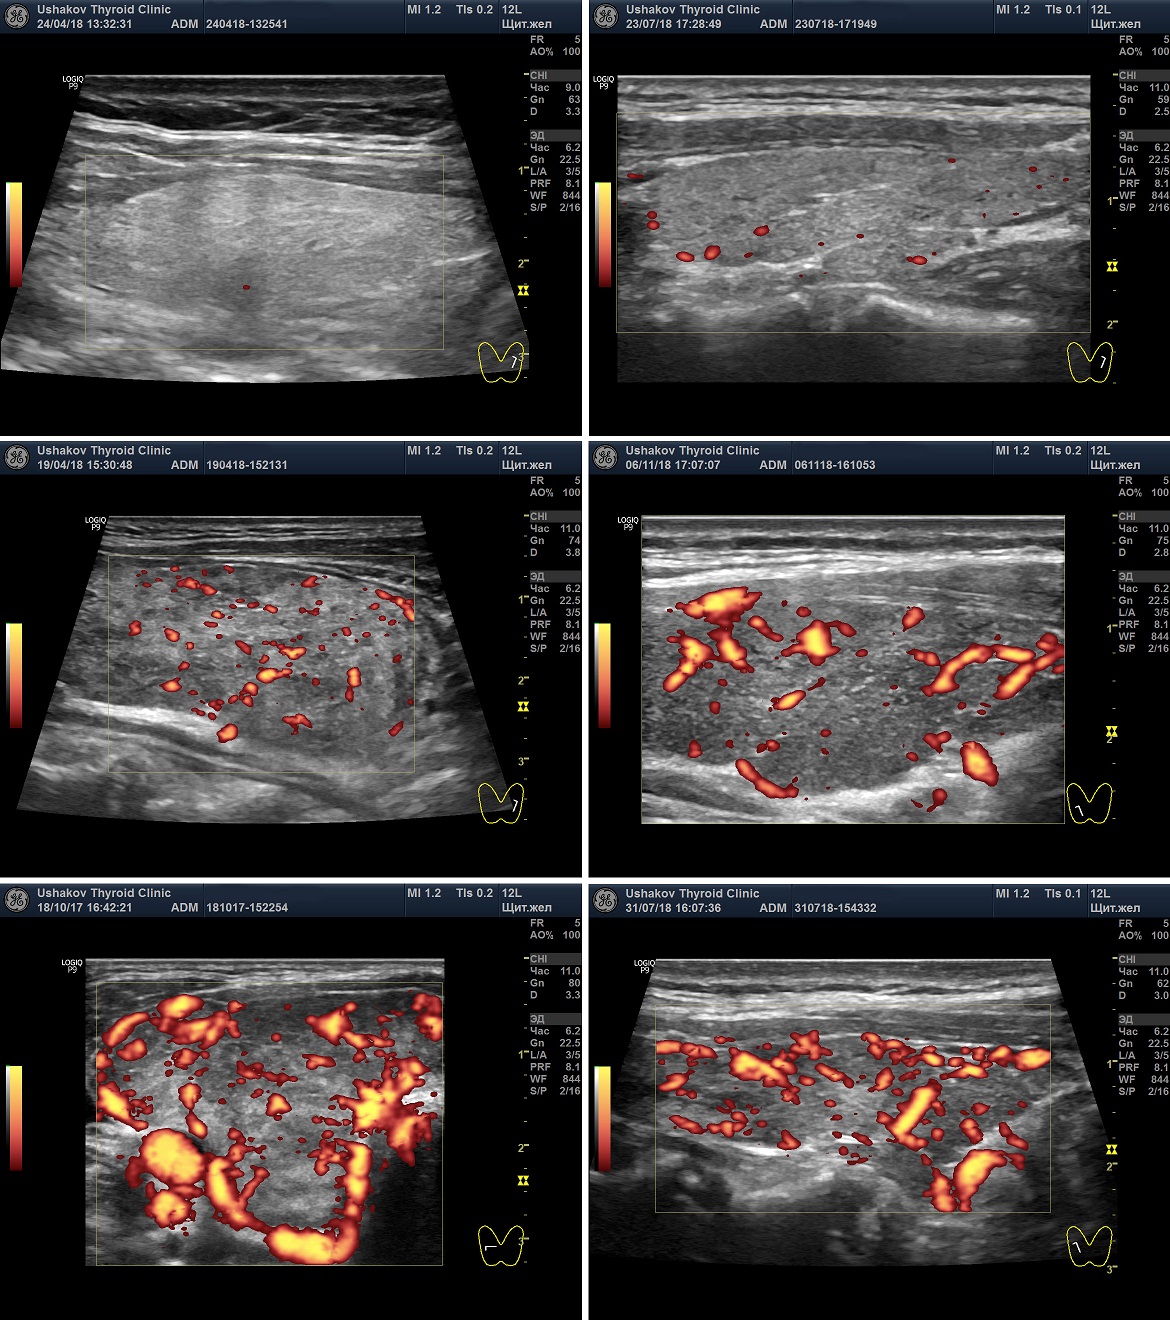

Кровоток в ЩЖ определяется в режиме ЦДК или ЭДК. Многие врачи применяют ЦДК, а не ЭДК, несмотря на меньшее количество искажений при ЭДК. Наша Клиника предлагает всем коллегам выполнять оценку интенсивности кровотока в ЩЖ с помощью ЭДК, а скорость крови в режиме ЦДК, так как ЦДК позволяет цветом различать артерии от вен.

Рисунок 2. Два варианта ультразвукового допплеровского режима ― ЦДК (цветовое допплеровское картирование) и ЭДК (энергетическое допплеровское картирование). Программа УЗ-аппарата показывает сосуды цветом. Красным и синим при ЦДК и алым ― при ЭДК. При ЦДК видны сосуды (артерии и вены), несущие кровь в разных направлениях). При ЭДК не видно направления течения крови, но меньше погрешностей.

Существуют 6 вариантов интенсивности кровотока в ткани щитовидной железы:

• Ослабленный,

• Нормальный (в составе нормального – оптимальный),

• Малого усиления,

• Умеренного усиленный,

• Значительно усиленный,

• Очень значительно усиленный.

Ослабленная интенсивность кровотока ― сосудистые элементы не видны или имеется 1-2 малого диаметра.

Нормальная интенсивность кровотока ― сосудистые элементы в доле ЩЖ от 3-4 до 10, без расширения магистральных сосудов.

Оптимальная интенсивность кровотока ― сосудистые элементы в доле ЩЖ около 5-7, без расширения магистральных сосудов.

Малое усиление интенсивности кровотока ― сосудистые элементы в доле ЩЖ от 10-12 до 20-25, с расширением некоторых сосудов.

Умеренное усиление интенсивности кровотока ― сосудистые элементы в доле ЩЖ от 20-25 до 35-40, с расширением магистральных сосудов внутри и по периметру доли.

Значительное усиление интенсивности кровотока ― сосудистые элементы в доле ЩЖ более 40, с расширением многих сосудов.

Очень значительное усиление интенсивности кровотока ― почти полное заполнение щитовидной железы сосудистыми элементами.

Рисунок 4. УЗИ ― допплеровское исследование интенсивности кровотока щитовидной железы. Показаны несколько вариантов: Ослабленный кровоток, нормальный кровоток, Малое усиление кровотока, Умеренное усиление кровотока и Значительное усиление кровотока.